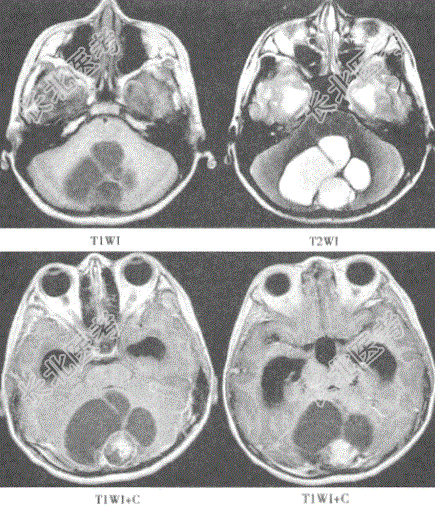

- 单项选择题患儿,10岁。头晕来院, 影像学检查如下图。该患儿最有可能的诊断是( )。

A、转移瘤

B、颅咽管瘤

C、髓母细胞瘤

D、血管网状细胞瘤

E、毛细胞型星形细胞瘤